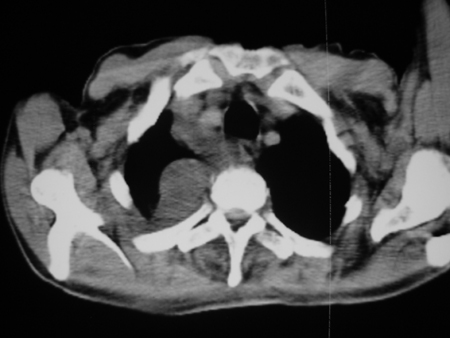

男77岁,胸痛就诊

右侧胸腔积液,部分包裹,右下肺膨胀不全,右下肺感染。

考虑右肺门占位并下叶不张 右胸包裹积液

右侧胸腔积液,部分包裹,右下肺膨胀不全